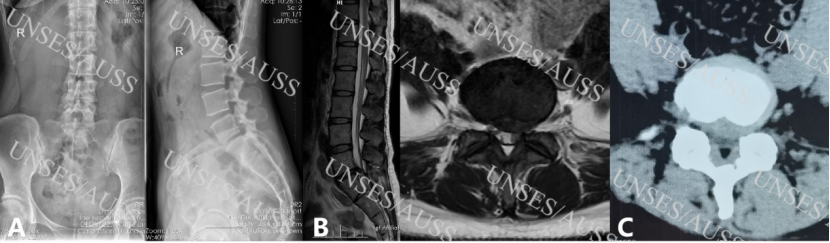

患者女性,38岁,腰5/骶1椎间盘突出(左侧),术前影像见图1。

图1 术前影像 A 腰椎正侧位X线片;B腰椎核磁共振提示腰5/骶1左侧椎间盘突出;C腰椎CT平扫提示腰5/骶1左侧椎间盘突出。